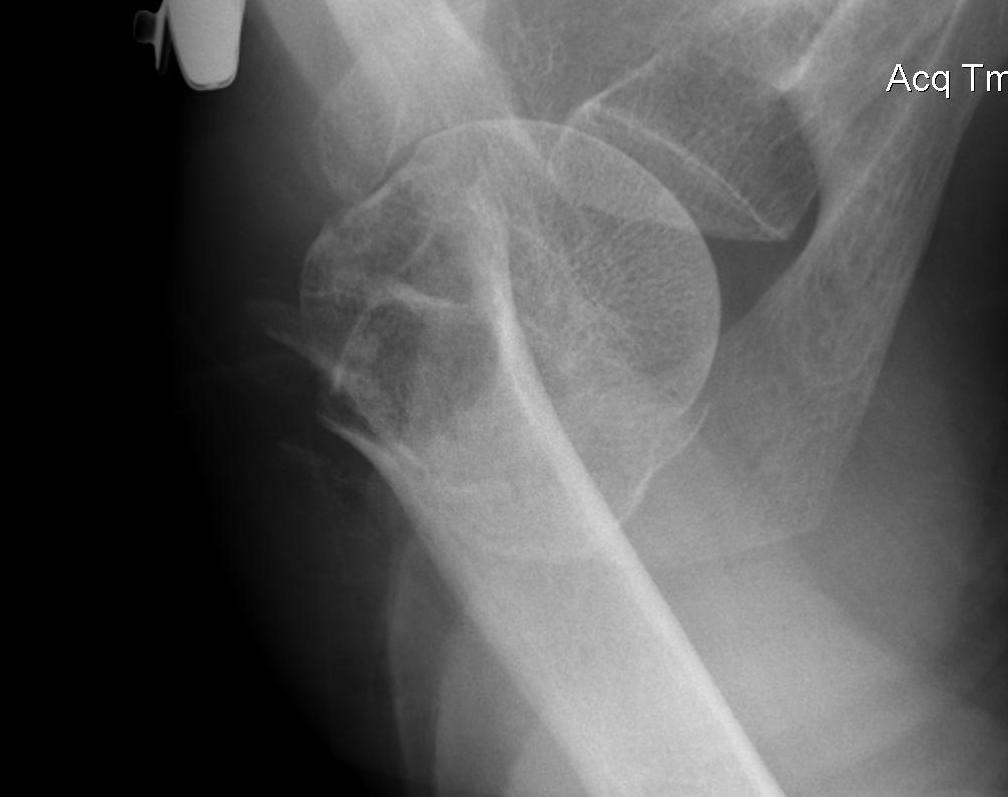

proximal humerus fracture Background ORIF with locking plate Arthroplasty Greater tuberosity fractures Lesser tuberosity fractures / avulsions Book traversal links for Proximal humerus fractures ‹ Pectoralis Major Tears Up Background ›